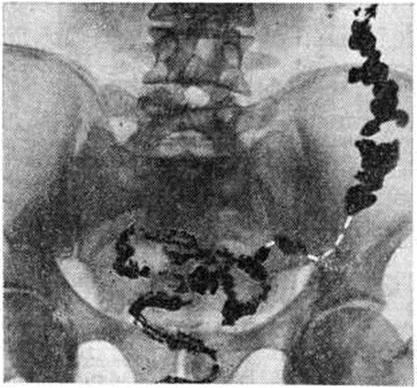

Рис. 3.

Рентгенограмма толстой кишки при гиперкинетическом запоре (колит), исследование с помощью контрастной клизмы: отдельные участки кишки спастически сокращены; имеют вид шнура.

При первичных Запоры обычно обнаруживают снижение моторной функции, повышение, или понижение тонуса кишки. Эти изменения могут распространяться на всю кишку или на отдельные её сегменты (рисунок 1). Рельеф слизистой оболочки имеет нормальный или несколько «раздражённый» характер (ирритационный рельеф): складки приподняты, расположены более продольно или поперечно, но лишены, признаков воспаления. Смещаемость кишки не нарушена. При гиперкинетических Запоры замедление пассажа бария сочетается с регионарным спазмом и глубокой, нередко сегментирующей гаустрацией в виде многочисленных перетяжек (рисунок 2). Спазмированный отдел кишки иногда имеет вид тонкого шнура (рисунок 3). Реже, при атонических Запоры, обнаруживают пониженный тонус всей толстой кишки или отдельных её сегментов, сопровождающийся расширением просвета, поверхностной сглаженной гаустрацией.